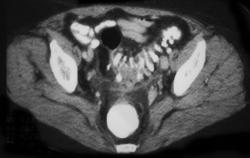

Pelvic Abscess S/P Colon Resection